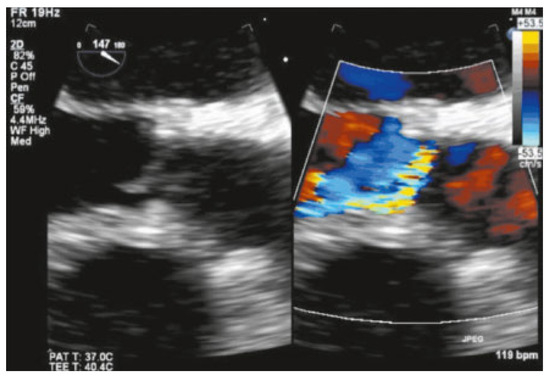

Value of Echocardiography in Differentiation of Acute Dyspnoea

by Ioannis Kapos and Felix C. Tanner

Echocardiography is one of the most effective imaging modalities for investigation of patients with acute dyspnoea. This review summarises appropriateness criteria and current guidelines for the use of cardiac ultrasound in common clinical scenarios presenting with acute dyspnoea, and illustrates such scenarios with [...] Read more.

Echocardiography is one of the most effective imaging modalities for investigation of patients with acute dyspnoea. This review summarises appropriateness criteria and current guidelines for the use of cardiac ultrasound in common clinical scenarios presenting with acute dyspnoea, and illustrates such scenarios with typical echocardiographic findings. Full article

Show Figures

Figure 1